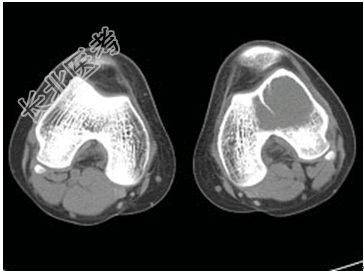

- [材料题] 患者,男,33岁,左股骨肿块半年余,无明显症状,查体一般情况良好。

- 简答题1、结合所提供的图像,该患者诊断为?